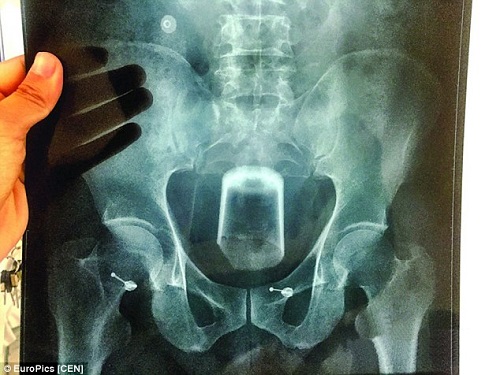

Bị táo bón lâu ngày không khỏi, một người đàn ông nảy ra ý tưởng nhét cốc bia vào hậu môn để chữa táo bón. Không ngờ…

Theo như lời người đàn ông giấu tên thì anh muốn làm dễ chịu đi căn bệnh táo bón của mình.

Hậu quả là chiếc ly với đường kính hơn 7cm đã bị mắc kẹt bên trong đại tràng của anh, khiến anh phải chịu đựng những cơn đau khủng khiếp nhất.

Anh đã trải qua hơn ba cuộc phẫu thuật tại bệnh viện Wuxi Central Hospital để gắp từng mảnh thuỷ tinh ra khỏi cơ thể.

Theo lời bác sĩ Li Chunwei, người đã thực hiện ca phẫu thuật trên: "Hằng năm chúng tôi tiếp nhận khoảng bốn đến năm tai nạn hi hữu như thế này. Từ trái cà tím cho đến que gỗ đã từng bị mắc kẹt trong hậu môn của nạn nhân".